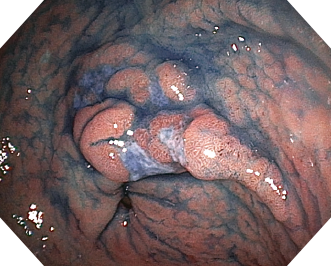

EVIS EXERAⅢ×GIF-H190N 症例画像